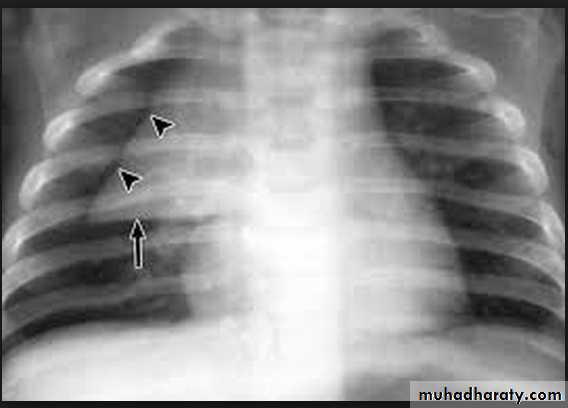

• Alveoiar oedema (‘Bat’s wings’)

• Kerlev B lines (interstitial oedema)

• Prominent upper lobe vessels

• Cardiomegaiy

• Pleura

• effusion

Kerley A lines (Arrows), Kerley B lines (arrowheads)